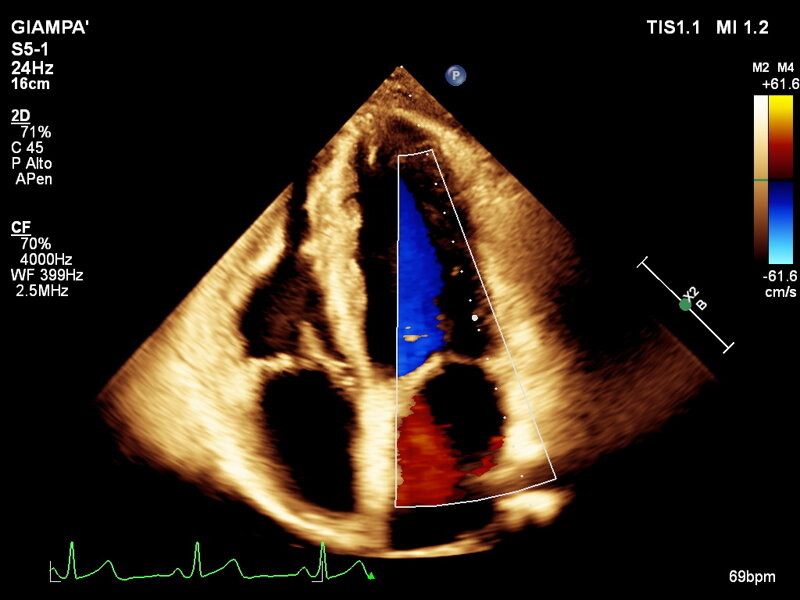

L’ecocardiografia è una metodica con cui si studiano il cuore e il flusso del sangue attraverso le valvole per mezzo degli ultrasuoni. permette di ottenere informazioni sulla contrattilità del cuore, sulla morfologia delle sue valvole e sul flusso del sangue nelle sue cavità, sia a riposo che dopo l’esercizio fisico